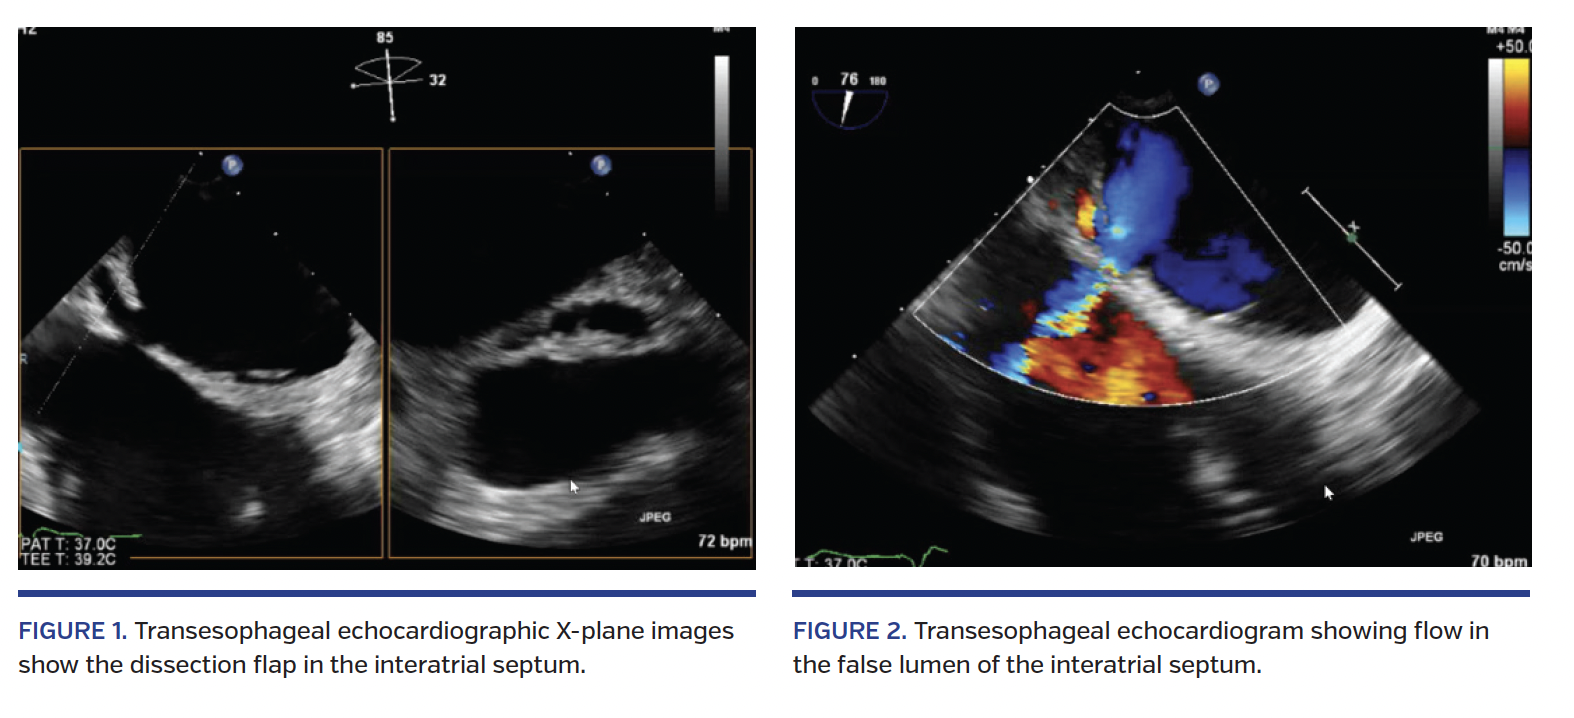

Transseptal puncture was performed under transesophageal echocardiographic (TEE) guidance using an 8.5 Fr SL1 guiding catheter and a transseptal radiofrequency needle (Baylis Medical). The MitraClip system was then advanced to the left atrium. A single MitraClip was deployed between the A2 and P2 segments of the mitral valve leaflets, leading to significant reduction in MR. Intraoperative TEE demonstrated interatrial septal dissection with a localized hematoma following removal of the MitraClip sheath (Figures 1 and 2; Video 1). After a multidisciplinary discussion, a conservative approach was recommended. The patient remained hemodynamically stable and asymptomatic post operation. At 1-month follow-up, echocardiogram showed resolution of the interatrial septal dissection.

Left atrial dissection is an exceedingly rare complication of cardiac surgery, with an incidence of 0.16%-0.84%. It is defined as a false, blood-filled cavity or lumen from the mitral annular area to the left atrial free wall or into the atrial septum, creating a new chamber with or without communications into the true left atrium, and is most commonly associated with mitral valve surgery. We report the first case of interatrial dissection and hematoma in association with the MitraClip procedure. The reported mortality rate in the surgical literature is 13.8%. Hemodynamically stable patients can be managed conservatively, with echocardiographic imaging, often with resolution of the dissection over the course of weeks.